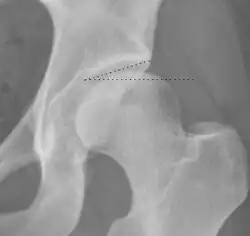

Radiograph of a cam type impingement.

Radiograph of a pincer type impingement.